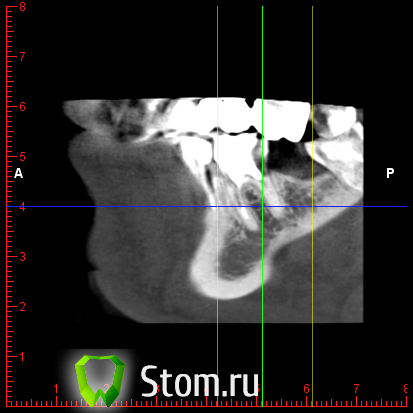

y2006 Опубликовано 3 мая, 2012 Автор Поделиться Опубликовано 3 мая, 2012 (изменено) прошу проконсультировать по поводу зуба 46. вопрос стоит в лечении и протезировании коронкой или удалении и заменой имплантом, правда ли что есть показания к удалению - перфорация корня? файлы для Romexis_Viewer по ссылке: (чуть позже)к сожалению не знаю как по другому выложить Изменено 3 мая, 2012 пользователем y2006 Ссылка на комментарий

y2006 Опубликовано 3 мая, 2012 Автор Поделиться Опубликовано 3 мая, 2012 снимок Ссылка на комментарий

y2006 Опубликовано 3 мая, 2012 Автор Поделиться Опубликовано 3 мая, 2012 (изменено) какие есть методы лечения? или есть необходимость в дополнительных проекциях? Изменено 3 мая, 2012 пользователем y2006 Ссылка на комментарий

y2006 Опубликовано 5 мая, 2012 Автор Поделиться Опубликовано 5 мая, 2012 (изменено) КТ IMAGES.rar46 зуб Изменено 5 мая, 2012 пользователем y2006 Ссылка на комментарий